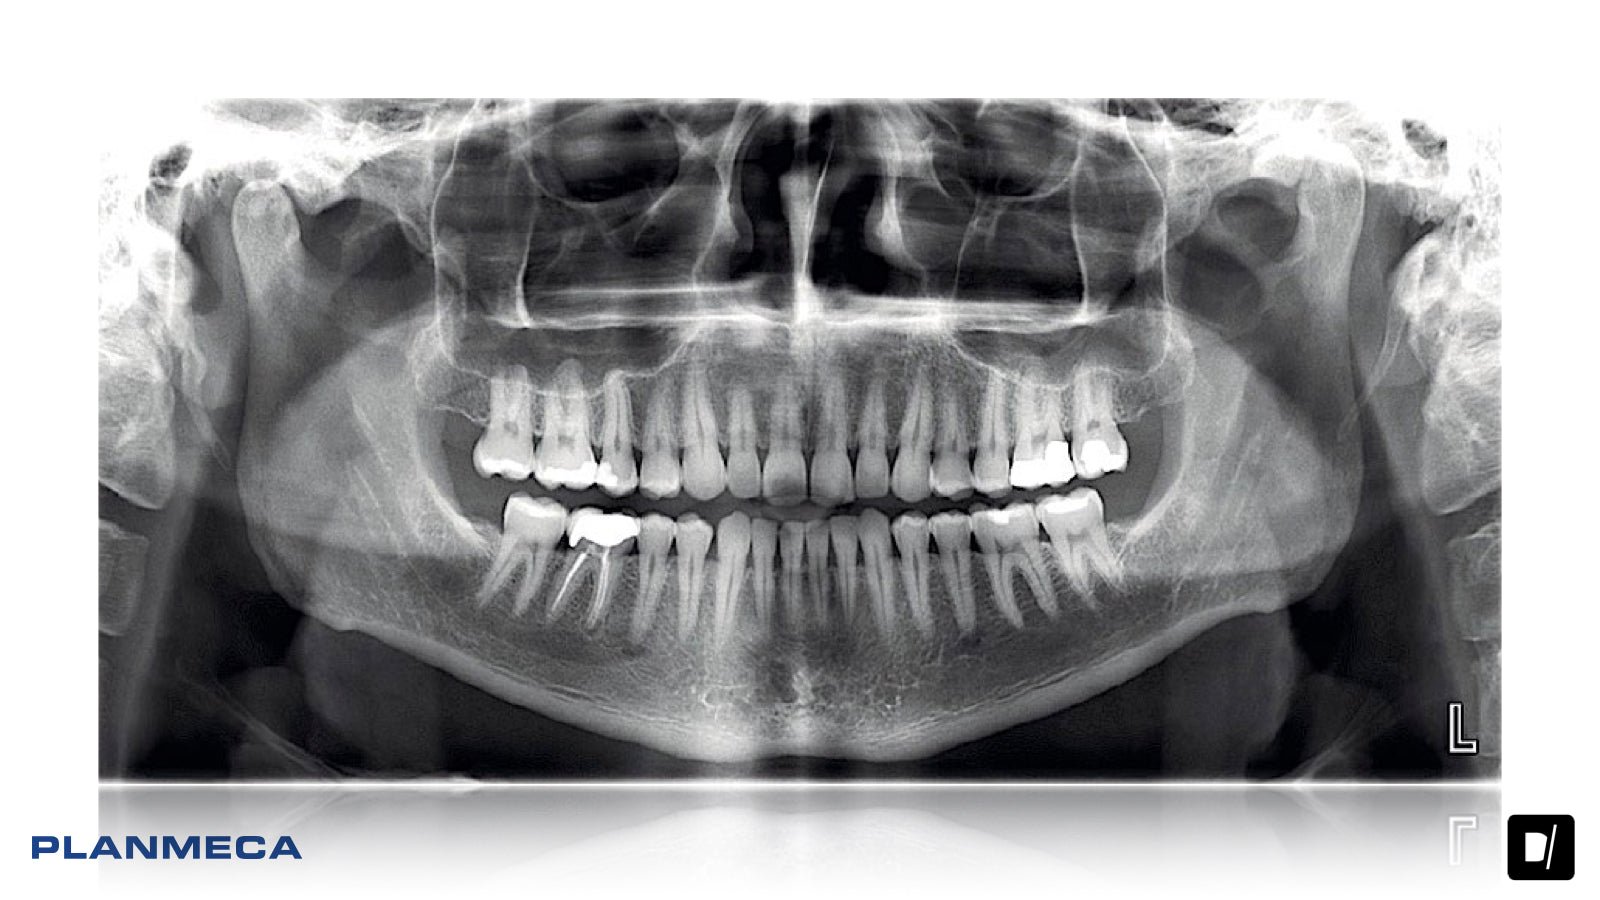

• Planmeca ProMax® 2D es un moderno y completo equipo de radiología oral para el procesamiento de imágenes maxilofaciales. Sus principios de diseño y funcionamiento se basan en las investigaciones científicas y tecnológicas más recientes. Las unidades son capaces de satisfacer incluso las necesidades más exigentes de la radiología dental moderna.

Las unidades de procesamiento de imágenes panorámicas Planmeca ofrecen una avanzada y versátil experiencia de imágenes 2D. Desde el posicionamiento flexible del paciente hasta las innovaciones creativas y la alta calidad de la imagen, representan las imágenes dentales 2D en su máxima expresión.

Las unidades Planmeca ProMax 2D ofrecen la más amplia variedad de programas de procesamiento de imágenes. Se encuentran disponibles distintos programas de imágenes panorámicas, así como opciones para imágenes de ATM, senos y tomográficas. Las unidades también tienen un modo para niños que permite obtener imágenes a dosis más bajas al reducir el área de procesamiento de imágenes y los valores de exposición.

Tecnología panorámica avanzada

Nuestra tecnología patentada SCARA (Selectively Compliant Articulated Robot Arm / Brazo Robot Articulado Selectivamente Adaptable) garantiza una geometría de imágenes anatómicamente precisa, lo cual genera imágenes claras y sin errores. Con Control de Exposición Dinámico (DEC), las unidades miden la transparencia de radiación del paciente y ajustan automáticamente los valores de exposición.